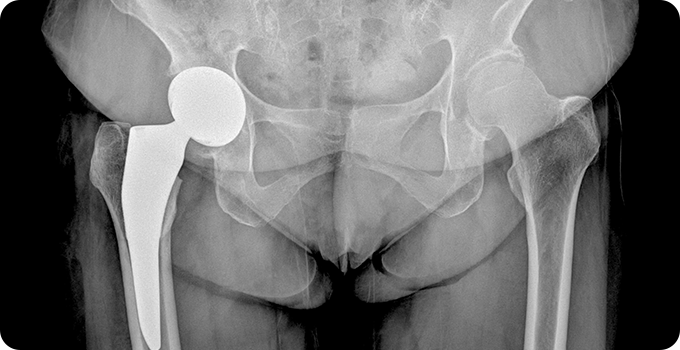

인공관절 수술

대퇴골두 무혈성 괴사의 인공관절 수술은 괴사가 심할 경우 시행됩니다. 고관절 인공관절 치환술은 대퇴골두와 비구를 교체하여 통증을 완화하고 기능을 회복시킵니다. 부분 고관절 치환술은 대퇴골두만 교체하는 방법으로, 비구가 건강할 때 선택됩니다. 수술 후 재활 치료를 통해 관절 기능과 근력을 회복하는 과정이 중요합니다.